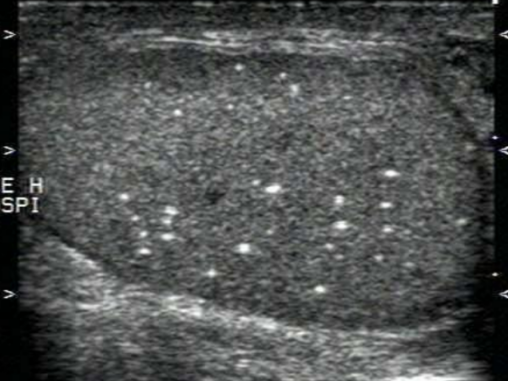

3.睾丸微石症

睾丸生精小管上皮细胞萎缩坏死后脱入生精小管腔内,以其为中心,糖蛋白和钙盐呈环形沉积。可能与精索静脉曲张、隐睾及睾丸发育不良等有关。

超声表现:双侧、散发、均匀分布的“满天星”表现;每个切面点状强回声5个以上,直径<3mm。虽然微石症是良性病变,但需密切随访。